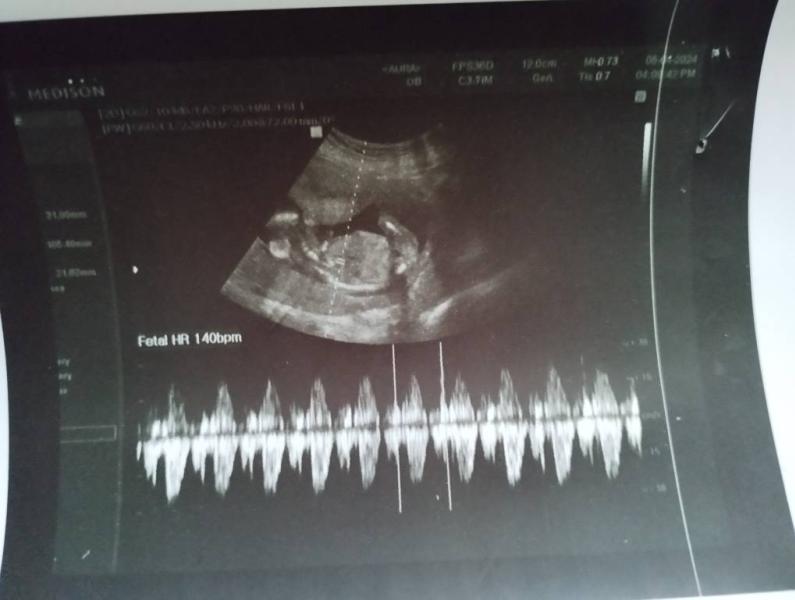

Такой вопрос, а вот справа от малыша это там не место второго?

На узи показалось что там справа голова была🙈

Фото в 12 недель 🤰